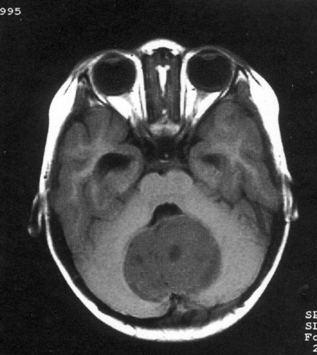

病历摘要:??患儿男性,11岁。半年前开始出现行走不稳,常无故跌倒。半月前出现发作性剧烈头痛,伴恶心呕吐。体检:T36℃,P100次/分,R22次/分,B...

问题 病历摘要:??患儿男性,11岁。半年前开始出现行走不稳,常无故跌倒。半月前出现发作性剧烈头痛,伴恶心呕吐。体检:T36℃,P100次/分,R22次/分,BP100/60mmHg,神清,言语较缓慢,双眼外展约不及边,双眼侧视时有小幅度水平眼震。四肢肌力正常,右上肢肌张力较低,坐位姿势不稳,常不自主摇晃,双上肢指鼻不准,行走蹒跚步态,足距扩大,身前倾。 下一步应首先行何种后续治疗?提示:经腰穿置管脑脊液外引流等处理,脑脊液渗漏停止。肿瘤病理为髓母细胞瘤。